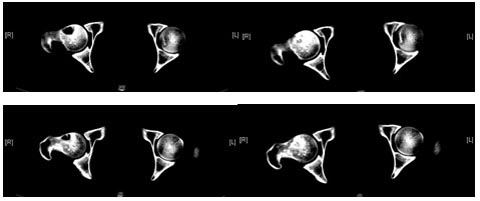

术前CT 术后8月CT

典型病例2:男性,26岁,特发性股骨头缺血性坏死。术前CT右侧股骨头内可见明显囊性变。术后8个月CT见囊性区消失,囊内内植骨愈合。